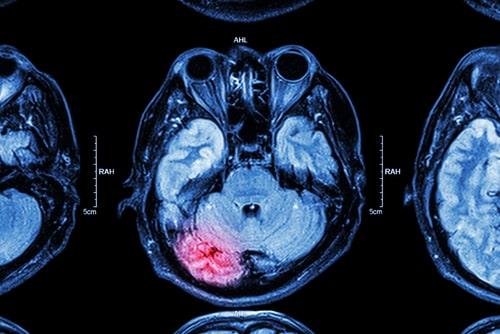

What to Know About CTE

In recent years, there has been increasing awareness of the dangers that professional athletes face due to the high risk of serious brain injury. The risk is heightened if you play a sport with a higher chance of repeated trauma to the head, like in hockey, wrestling, and football for example. The repeated hits to the head suffered by someone who has been playing a particular sport professionally for several years can lead to the development of what is known as chronic traumatic encephalopathy (CTE), which can result in severe disability. If a loved one suffered brain trauma that developed into CTE, speak with a knowledgeable Naperville, IL personal injury attorney with experience in similar cases to understand how to move forward.

In recent years, there has been increasing awareness of the dangers that professional athletes face due to the high risk of serious brain injury. The risk is heightened if you play a sport with a higher chance of repeated trauma to the head, like in hockey, wrestling, and football for example. The repeated hits to the head suffered by someone who has been playing a particular sport professionally for several years can lead to the development of what is known as chronic traumatic encephalopathy (CTE), which can result in severe disability. If a loved one suffered brain trauma that developed into CTE, speak with a knowledgeable Naperville, IL personal injury attorney with experience in similar cases to understand how to move forward.

What Happens When You Have CTE?

CTE is linked to repeated head trauma, and professional athletes are among the groups with the highest risk of developing it. This disease often gets worse over time and can even lead to dementia. There are four main stages of CTE, with the symptoms associated with these stages generally appearing between eight and ten years after the repetitive brain trauma. The stages are:

- Stage 1: Headaches, dizziness disorientation, and confusion

- Stage 2: Memory loss, impulsivity, social instability, and poor judgment

- Stages 3 and 4: Speech impediments, sensory processing disorder, movement disorders, depression, vertigo, tremors, dementia, and suicidal thoughts.

Unfortunately, there is no way to diagnose CTE during one’s life and no cure for it. There are tests that can be performed to diagnose CTE, but only during an autopsy. This makes the disease even more devastating. Not only is there no way to get better, but there is also nothing to help you or your loved one understand what is happening and why they are acting the way they are.